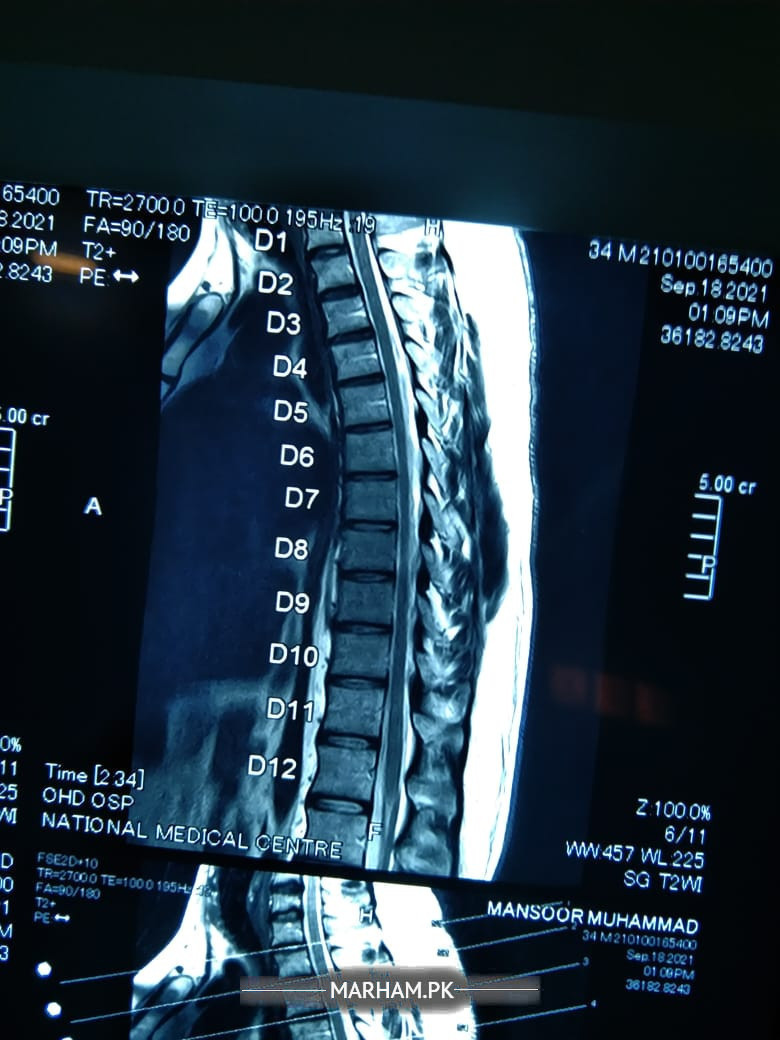

Asking For Self, Male 34, karachi

Muscler pain , urine control loss , Hath pair sunn hojaty hyn , almost 4 years sy yeh problem chal rhi hy medicines sy b ab koi faida nhy horha . need serous suggestions

MRi

current MRi